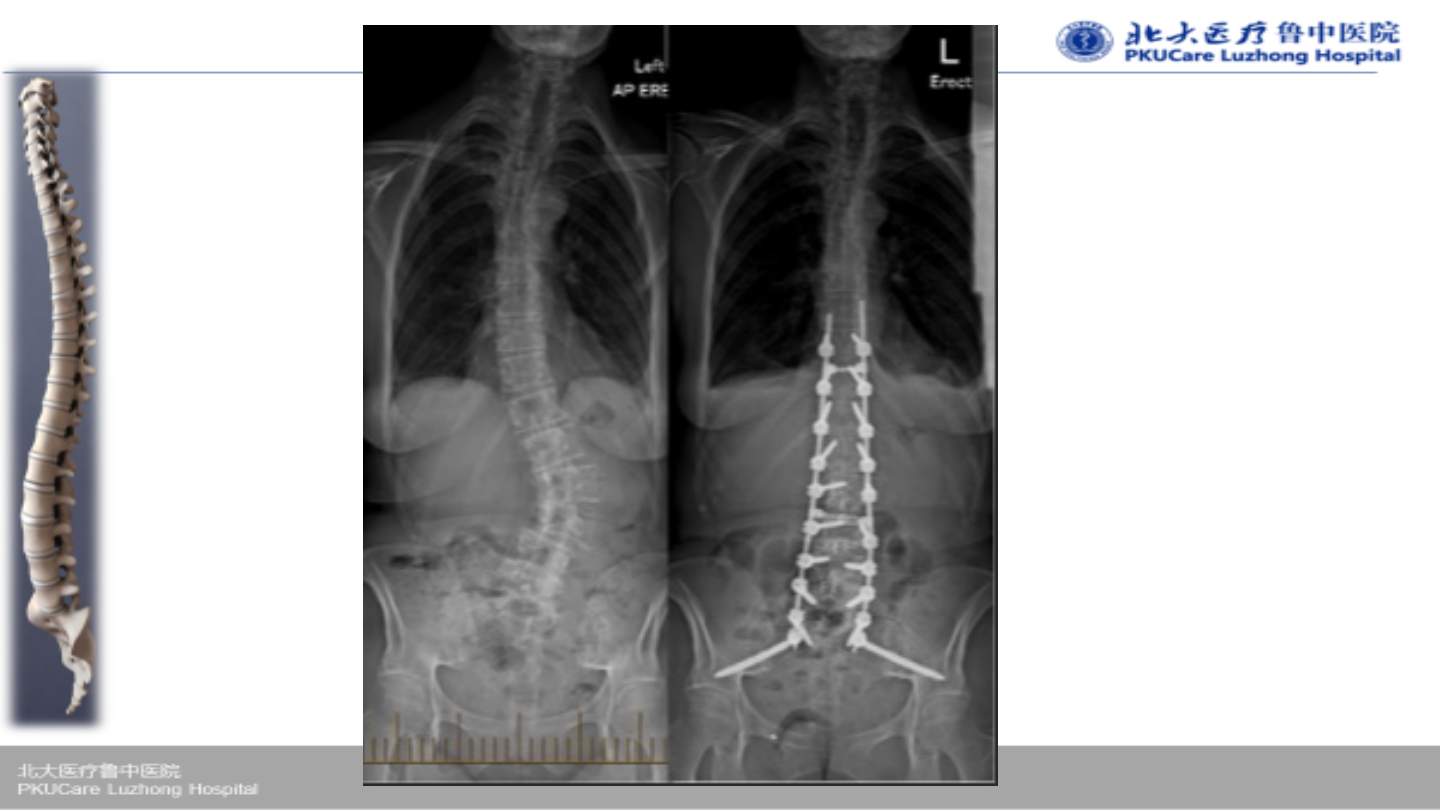

术后

Ø

VAS 3分

VAS

改善率

90%

ODI

82%